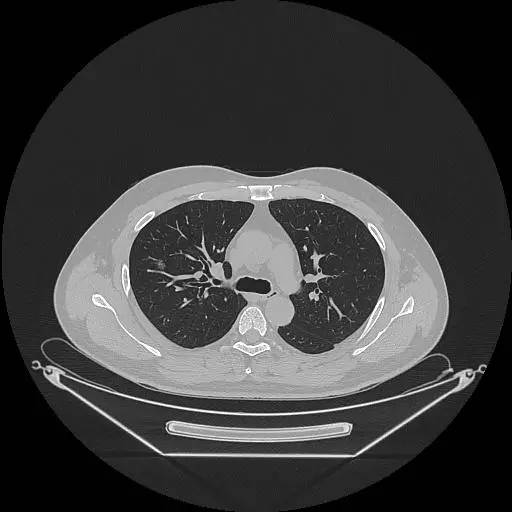

男,47岁,查体发现右肺小结节8月余。

右肺上叶可见直径约7mm磨玻璃样结节,其内见空泡影,有浅分叶及血管集束征象,增强扫描无强化,余肺、纵隔未见明显异常。

右肺上叶不典型腺瘤样增生(AAH)

AAH的影像学特点为呈类圆形小病灶,边界清楚,淡至中等密度均匀的毛玻璃或磨砂玻璃阴影,不遮蔽其下的肺实质,多数在5 mm以下。